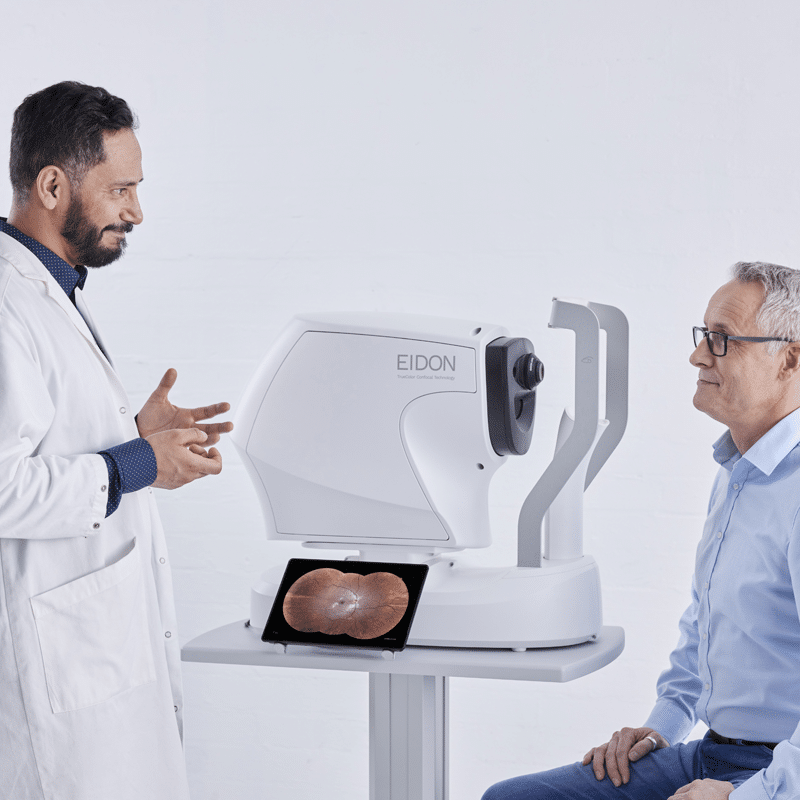

- Short exam time for enhanced patient comfort

- Quick and easy-to-use – fully automated

Multiple users sharing, viewing and analysing

The EIDON AF Remote Viewer (RV) makes remote data review easy, allowing any computer or laptop on the same network (LAN) to review remotely EIDON AF images. Data access and analysis is possible on multiple review stations.